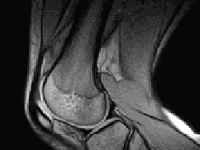

Rotura de Menisco

El menisco es un cartílago que se encuentra en la zona interna de la articulación de la rodilla.La función que cumple es la de...

Tratamiento de la Rotura de Menisco

Tratamiento Conservador del Menisco

El tratamiento inicial de un menisco roto se dirige a:reducir el dolor e inflamación de la rodilla.Su médico puede recomendarle...